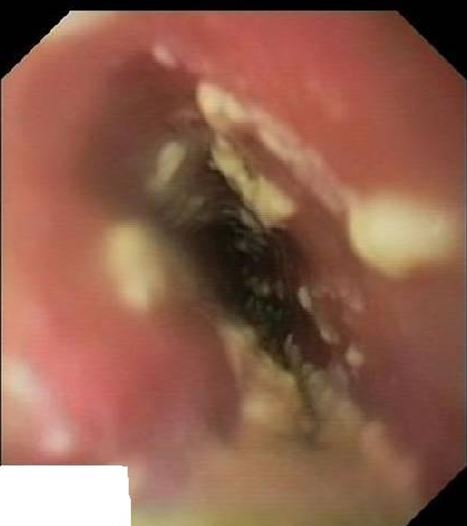

Paciente hombre de 48 años, ExADVP, VIH positivo Categoría C2 diagnosticado en 1986. Nadir de CD4 de 815 cél/μl. Tuberculosis diseminada con afectación pulmonar, ganglionar e intestinal en Agosto 2007, correctamente tratada. Hepatitis crónica VHC con respuesta virológica sostenida tras tratamiento antivírico en 2004. No recibe tratamientos habituales y nunca ha recibido TARGA.

El último control realizado un mes antes de la consulta mostraba una cifra de CD4 de 378 (20%) cél/μl y ARN-VIH: 28.723 copias/ml. Se realiza una gastroscopia que muestra la presencia de múltiples placas blanquecinas adheridas a lo largo de todo el esófago. Estómago y duodeno, sin alteraciones. (Figura 1 ).